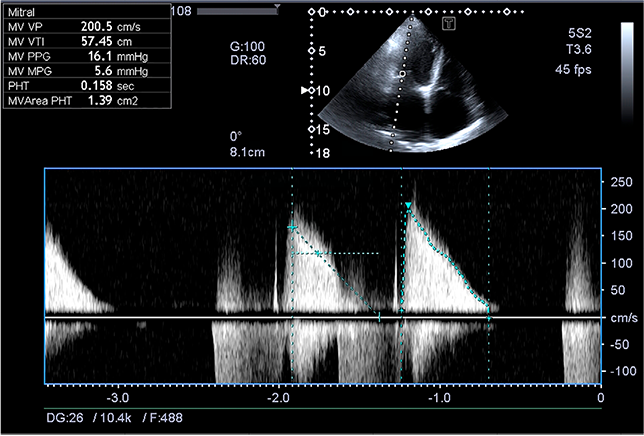

В сообщении представлено клиническое наблюдение повторной операции у пациента 55 лет с ревматическим стенозом митрального и функциональной недостаточностью трикуспидального клапана через 38 лет после имплантации шарового протеза в аортальную позицию. По данным эхокардиографии, пиковый трансмитральный градиент 16 мм рт. ст., средний — 5,5, площадь 1,3 см2, регургитация 3-й ст. На трикуспидальном клапане регургитация 3-й ст.

Удовлетворительные гемодинамические показатели работы шарового протеза (максимальная скорость кровотока 2,65 м/с, пиковый градиент 30 мм рт. ст., средний — 18, регургитации нет), отсутствие клапанозависимых осложнений позволили ограничиться протезированием митрального и пластикой трикуспидального клапанов без замены аортального протеза, что сократило продолжительность операции и снизило риск осложнений. Осмотр пациента через 2 года после операции, его активный образ жизни, удовлетворительные гемодинамические параметры при обследовании подтверждают правильность тактики. Результат доказывает возможность хирургического лечения митрального порока в отдаленные сроки после протезирования аортального клапана хорошо функционирующим шаровым протезом без его замены.